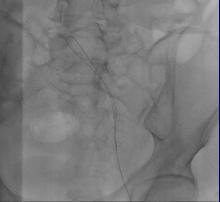

急诊造影:大腿段腘静脉通畅,股静脉通畅,见图3

图3